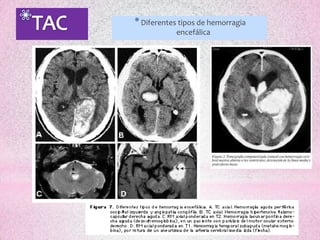

* Diferentes tipos de hemorragia

encefálica

* Diferentes tiposde hemorragia encefálica